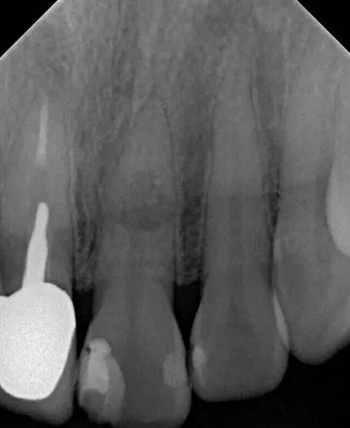

左上中切牙近遠(yuǎn)中有牙色充填體,邊緣繼發(fā)齲,牙齒不松動(dòng),輕微叩痛,患牙冷測(cè)遲鈍,牙齦未見異常。X線片示:充填體周圍繼發(fā)齲壞近髓,根中部大面積低密度影,蟲噬狀,內(nèi)部結(jié)構(gòu)顯示不清晰,根尖周未見異常。錐形束CT(CBCT)顯示根中部?jī)?nèi)吸收多處可疑穿孔,缺損內(nèi)可見菜花狀鈣化物影像

診斷:左上中切牙牙根內(nèi)吸收。治療計(jì)劃:左上中切牙根管治療,全冠修復(fù)。 治療過程:患者知情同意。使用含1/100,000腎上腺素的4%鹽酸阿替卡因(碧蘭麻,艾龍)局部浸潤(rùn)麻醉,橡皮障隔濕。去腐未盡露髓,露髓孔出血多。開髓,使用10#不銹鋼K銼(MANI,日本)探查根管,根管中段有鈣化物阻擋,不能達(dá)到牙根全長(zhǎng)(圖3A)。在顯微鏡下(Leica M400E,萊卡, 德國(guó)) 使用超聲尖(E1根管治療超聲尖,啄木鳥公司,中國(guó))通開,采用根管長(zhǎng)度測(cè)量?jī)x(Root ZX, Morita公司,日本)加診斷絲片法(圖1B)測(cè)量根管長(zhǎng)22 mm。使用控制扭矩馬達(dá)(X-smart,登士柏)和鎳鈦旋轉(zhuǎn)器械(Hero 642, Micromega)根管預(yù)備,根管預(yù)備過程中使用5.25%次氯酸鈉溶液沖洗。 根備完成后使用超聲蕩洗根管,5.25%次氯酸鈉溶液3 分鐘, 17% EDTA溶液1分鐘。干燥根管,使用螺旋充填器根管內(nèi)封氫氧化鈣糊,氧化鋅丁香油水門汀暫封。1周后患者復(fù)診,患者述無術(shù)后不適,檢查暫封完好,無叩痛,不松,牙齦無紅腫瘺管。使用橡皮障隔濕,去除暫封物,超聲蕩洗根管,5.25%次氯酸鈉溶液3 分鐘, 17% EDTA溶液1分鐘。干燥根管,牙膠尖(達(dá)雅鼎,中國(guó))和必蘭根充糊劑(Cortisomol, 艾龍公司,法國(guó))熱垂直加壓法根管充填。術(shù)后片顯示根充恰填,可見牙膠/糊劑被壓入鈣化物周圍和內(nèi)部縫隙內(nèi)